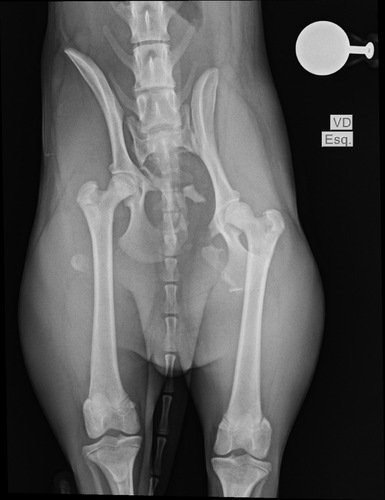

Tatu fugiu e foi atropelado, o motorista fugiu e não prestou socorro, ele teve 3 fraturas e terá que a realizar 3 cirurgias, fora exames e a internação na clínica  ver tudo

Tatu fugiu e foi atropelado, o motorista fugiu e não prestou socorro, ele teve 3 fraturas e terá que a realizar 3 cirurgias, fora exames e a internação na clínica